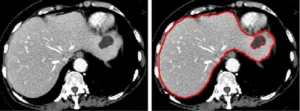

Medical image segmentation is the process of delineating specific regions of interest — organs, lesions, tumors, vessels — within imaging modalities such as CT, MRI, X-ray, ultrasound, and histopathology slides. Segmentation is not merely “drawing around stuff.” It is a structured, medically meaningful act that defines the ground truth from which all downstream AI learning flows.

Automated pre-segmentation tools can accelerate workflow, but they introduce systematic errors that, if uncorrected, get baked into the model during training. A model trained on imperfect ground truth learns to replicate those imperfections, including missed pathology boundaries, false inclusions, and anatomically incorrect delineations. Manual segmentation by trained clinical annotators, particularly those with clinical or radiological background ensures that:

Pathological edge cases and ambiguous boundaries are handled with domain reasoning, not algorithmic approximation. Anatomical context is preserved — what looks like noise to an algorithm is recognizable structure to a clinician. Rare disease presentations, artifact-prone scans, and low-contrast regions are correctly handled. Annotation guidelines can be applied consistently, reducing inter-annotator variability.